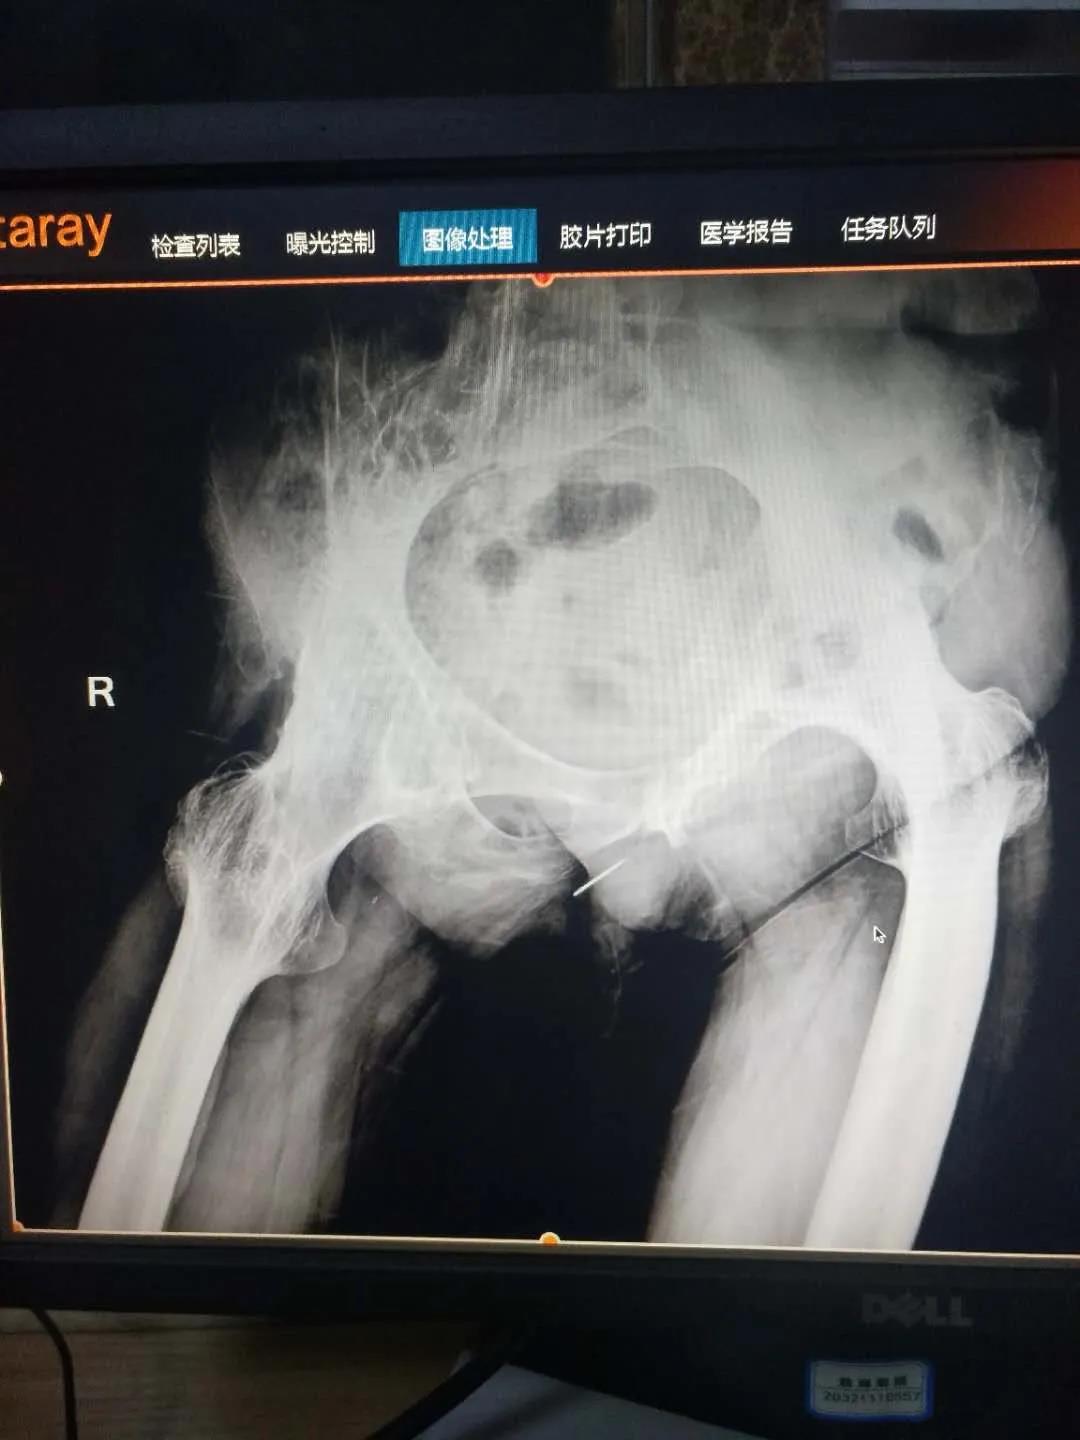

髖關節(jié)置換治療

髖關節(jié)疾病終末期股骨頭塌陷或關節(jié)破壞較重,只能采用髖關節(jié)置換、治療,骨二科采用微創(chuàng)Super-path入路和DAA入路進行髖關節(jié)置換,患者術后當天即可下床活動,術后無痛管理,加速患者術后康復及早日重返社會。

全髖關節(jié)置換